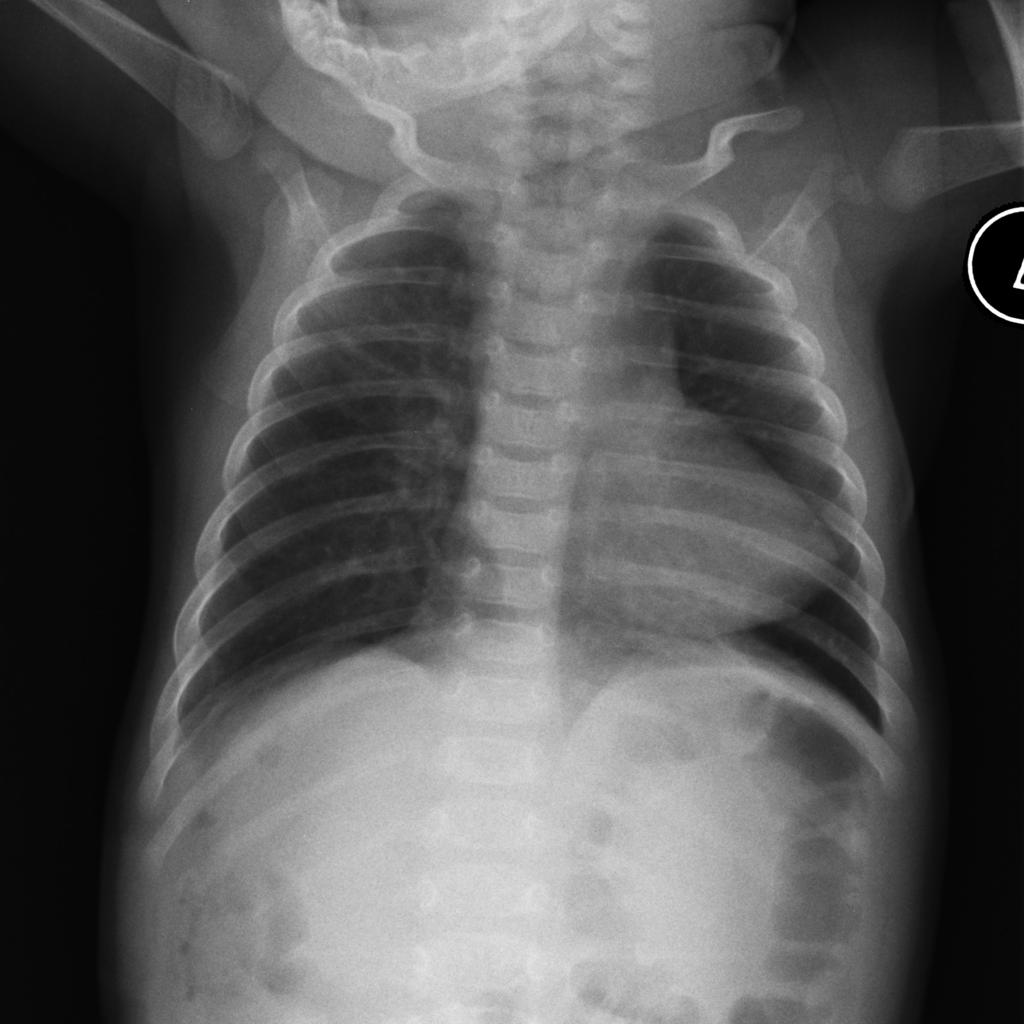

- Chest radiograph may show classic “egg of a string”

- Unobstructive – cardiomegaly with increased pulmonary markings, “snowman sign”

- Obstructive – small heart

“snowman sign” Case courtesy of Dr Aditya Shetty, Radiopaedia.org. From the case rID: 27800